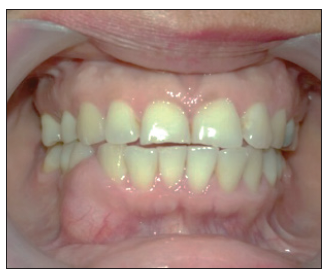

Al examen semiológico intraoral se evidenció tumefacción en la mandíbula, sin asimetría facial, en región parasinfisiaria a nivel de los dientes 43 y 44 por vestibular, que presentaron movilidad grado 2, de consistencia firme, indolora, de tamaño aproximado de 1 cm de diámetro, circunscrito, de base sésil y con mucosa de revestimiento, hidratada y rosada pálida igual a la mucosa adyacente, de evolución desconocido (figura 1). Se realizó inicialmente radiografías: panorámica y periapical, y se evidenció lesión radiolúcida circunscrita en región interproximal de órganos dentales 43 y 44 con desplazamiento de las raíces y con apariencia de pompas de jabón.